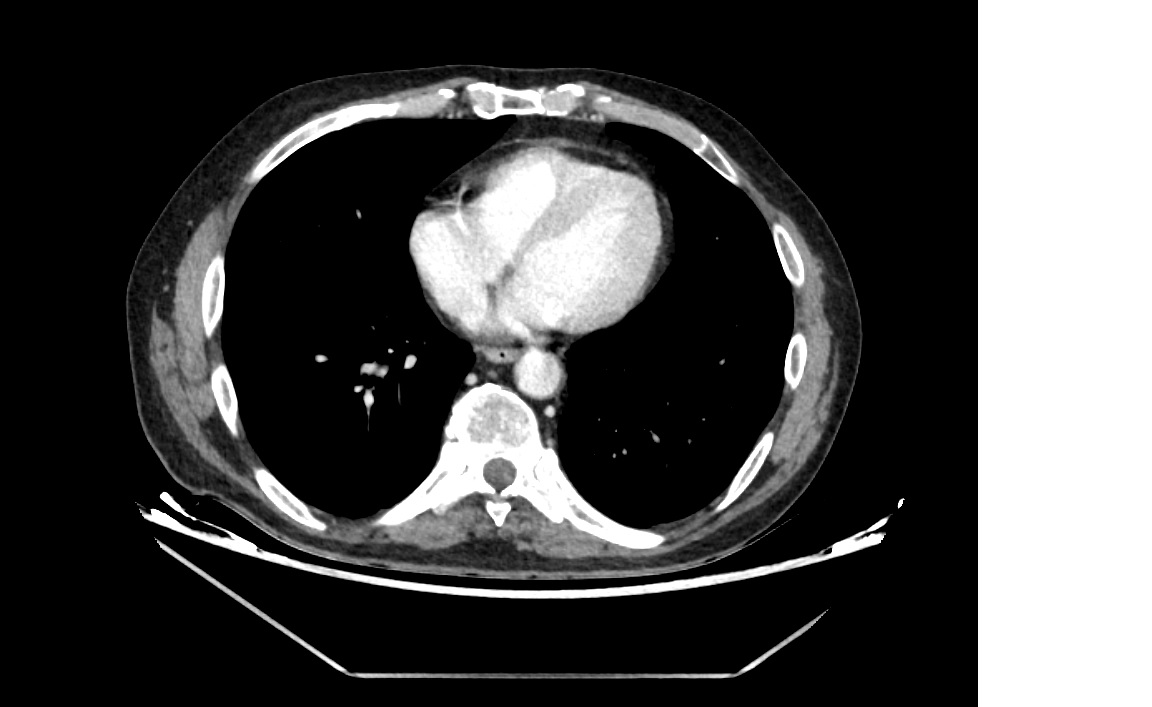

En el hospital se realiza TAC abdominopélvico observándose: signos de cistoprostatitis con abceso de 15 mm y hallazgo incidental de aneurisma de aorta abdominal infrarrenal (3,8x3,6 cm) con signos de rotura contenida y trombo mural excéntrico.

Hallazgo incidental de aneurisma aórtico abdominal con rotura contenida, planteando el dilema clínico entre infección activa y cirugía urgente. Problemas identificados: infección urinaria por E. coli y riesgo vital por aneurisma roto contenido.

3 días después se realizó sellado de rotura aórtica infrarrenal mediante endoprótesis con buen resultado intraoperatorio y postoperatorio. Evolución favorable, sin complicaciones. Alta con antibioticoterapia oral y seguimiento por Atención Primaria.